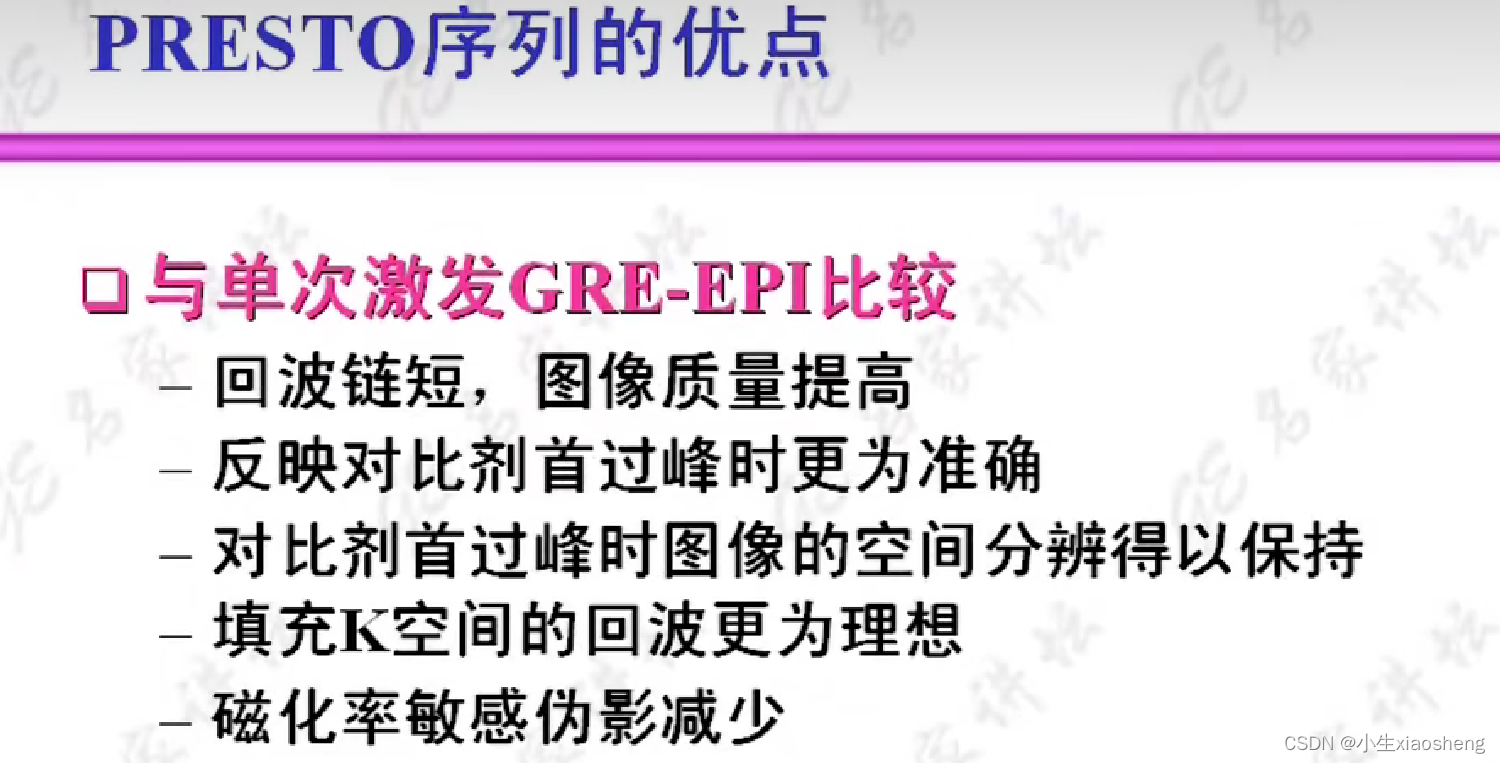

自旋回波--90度和180度填充K空间;反转恢复--在自旋的基础上两边加180度;梯度回波--消除每次脉冲留下的影响,以及波的次数;propeller==》K空间填充技术和FSE或FIR结合用于减少运行伪影;EPI==》采集方式,一次激发采集多个回波的形式但与单次不一样;PRESTO和GRASE==》前面几种的一种结合形成新的。

八、PRESTO和GRASE序列